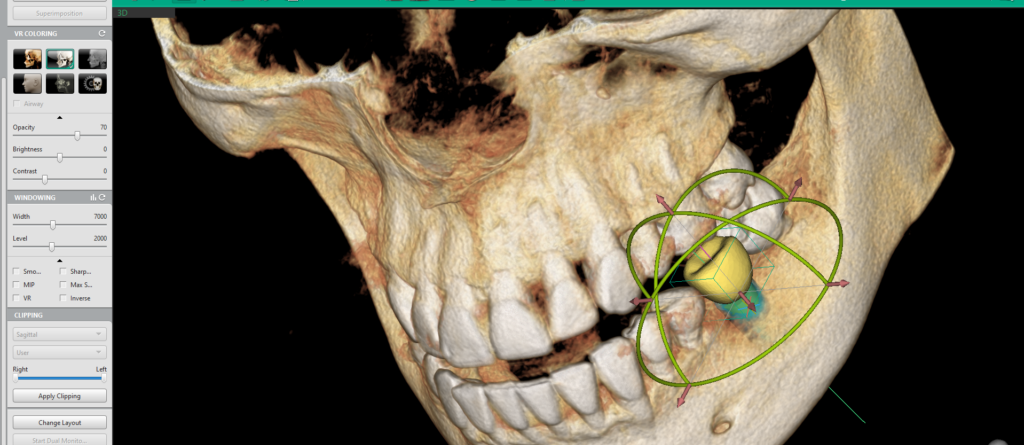

Odată selectată dimensiunea dorită printr-un click stânga, modelul implantului apare instantaneu în imaginea 3D, facilitând plasarea și verificarea sa în timp real.

2. Verificarea poziției implantului

În implantologie, verificarea poziției implantului este esențială pentru succesul procedurii și stabilitatea acestuia pe termen lung. Orice eroare de poziționare poate duce la complicații, de la integrarea deficitară a implantului în os, până la afectarea structurilor anatomice adiacente. Din acest motiv, Ez3D-i oferă o serie de instrumente avansate care permit verificarea multiplă a poziției în timpul plasării implantului, optimizând astfel fiecare etapă a procesului chirurgical.

Funcția Set MPR Axis este un instrument esențial pentru verificarea poziționării corecte a implantului, oferind o metodă rapidă și eficientă de analiză a sănătății osoase și a plasării implantului în raport cu structurile adiacente.

Printr-un simplu click dreapta pe implant și selectarea opțiunii „Set MPR Axis” din fila MPR, software-ul realiniază automat toate planurile imagistice conform poziției implantului. Această funcție oferă medicului o perspectivă detaliată asupra implantului în raport cu densitatea osoasă și permite ajustarea rapidă a poziției înainte de finalizarea procedurii.